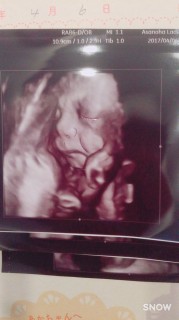

二人目☆男の子です! 1600gになっていました! いつもは手で顔を隠しているのにこの日は目を開けてこちらをチラっと見ていました!

29w3d約1400g 1人目女の子(2歳)で 2人目は男の子です。 今日初めてエコーで顔を見せてくれました! 顔が見えると更に可愛いさ倍増((*pq'v`*)) お姉チャンと似てる気が…